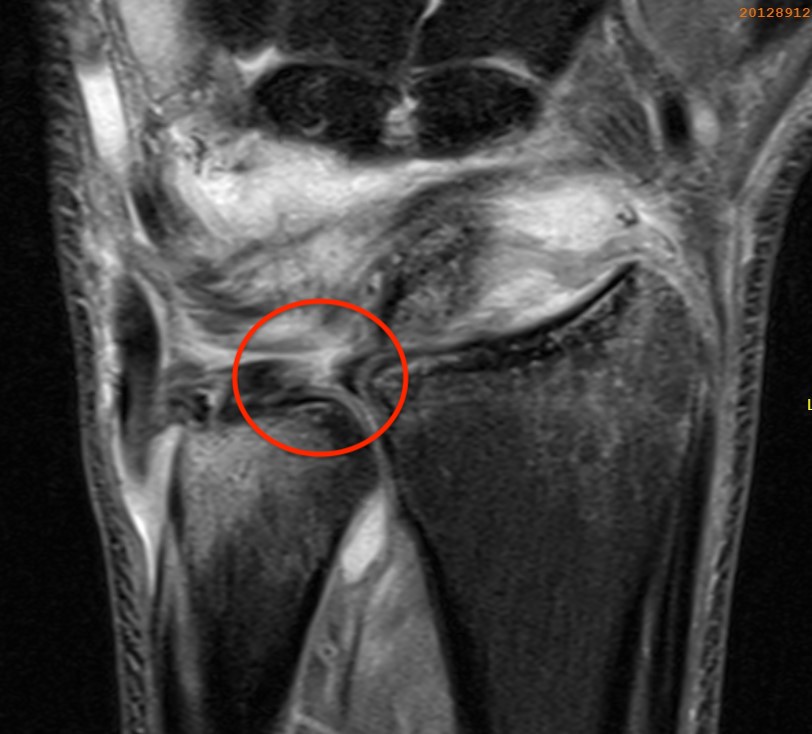

Ulno-carpal abutment

Ulnocarpal abutment and lunate chondromalacia

Class 2 Degenerative TFCC tears

Central TFCC tear with ulna positive variance an ulnocarpal abutment on MRI